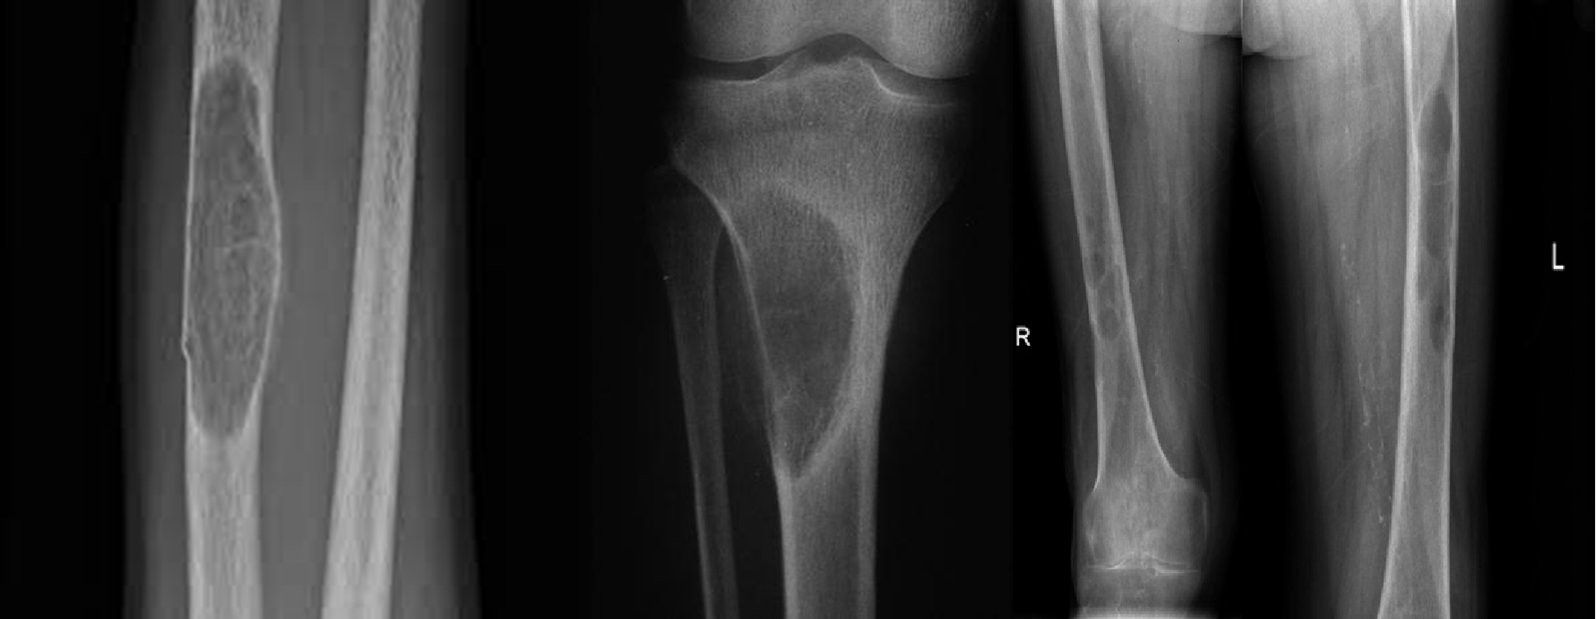

- Sub-periosteal resorption: middle phalanges, tibial shaft

Lytic lesions caused by hyperparathyroidism are called Brown tumors. The term âBrown tumorâ is a misnomer because it is not a true neoplasm.

- In hand, sub-periosteal bone resorption .This change usually happen in the middle phalanges, radial aspect in the 2nd or 3rd finger.

- Terminal tuft erosion.

Subperiosteal bone resorption (straight arrow), resorption of the tip of the terminal phalanx and the altered bone architecture. Arterial calcification is also present (curved arrow).